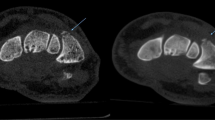

This study included 92 patients receiving conservative treatment for fractures of the shoulder, knee, ankle, or wrist who underwent SD-CT and ULD-CT at an interval of 1–2 weeks (mean, 8.85 ± 1.98 days); 24 patients (72 bones) had shoulder fractures, 17 patients (68 bones) had knee fractures, 25 patients (225 bones) had ankle fractures, and 26 patients (390 bones) had wrist fractures. Of these, 56 patients (65 fractured bones; 17 fractured shoulders, 14 fractured knees, 10 fractured ankles and 6 fractured wrists, with 1 bone fracture per joint; 1 fractured ankle and 8 fractured wrists, with 2 bone fractures per joint) had displaced fractures, and 36 patients (43 fractured bones; 7 fractured shoulders (Fig. 1a, b), 3 fractured knees (Fig. 1c, d), 12 fractured ankles and 7 fractured wrists, with 1 bone fracture per joint; 2 fractured ankles and 5 fractured wrists, with 2 bone fractures per joint (Figs. 2 , 3) had non-displaced fractures. Four non-displaced fractures were missed by ULD-CT (Fig. 2).

Diagnosis of non-displaced fracture of the shoulder (a, b) or knee (c, d) (red arrow). a and c: SD-CT images (subjective CT image quality and impact of subjective CT image quality on clinical decision-making, 5 points); b and d ULD-CT images (subjective CT image quality and impact of subjective CT image quality on clinical decision-making, 3 points)

Objective CT image quality (noise, SNR, CNR) was significantly improved for SD-CT compared to ULD-CT (F = 16.42~1808.07, p < 0.0001). CTc was significantly higher for ULD-CT compared to SD-CT (F = 23.97~136.48, p < 0.0001; Table 3) Scores for subjective CT image quality and the impact of subjective CT image quality on clinical decision-making were ≥ 3 points for SD-CT and ULD-CT, but were significantly improved for SD-CT compared to ULD-CT (Z = − (3.76–4.46), p < 0.0001) (Figs. 1, 2, 3, Table 4). ICC values for subjective CT image quality and the impact of subjective CT image quality on clinical decision-making for SD-CT and ULD-CT indicated good consistency (ICC = 0.65–0.99, Table 4).